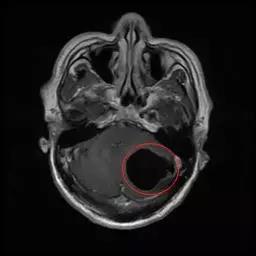

X光片显示,左小腿和右小腿分布着零散的囊虫,头部MR进一步显示,小脑半球内已聚集形成了一个较大的囊性占位……看着这些触目惊心的图片,刘宇(化名)觉得头脑发麻,没想到自己身上有这么多囊虫在潜伏。

(术前头部MR,左侧小脑半球内一较大的囊性占位,压迫小脑、脑干,为囊虫病变。“黑色空洞”部分即为囊虫病灶)

今年3月,刘宇连续两周头痛剧烈,走路不平稳,遂去广州的医院就医。据广东三九脑科医院神经外六科主任吴杰介绍,患者的影像检查提示颅内多发占位病变,结合病史,考虑为颅内多发脑囊虫病,于是为刘宇进行了“左侧小脑囊虫占位切除术”。术后病理提示为脑囊虫病。